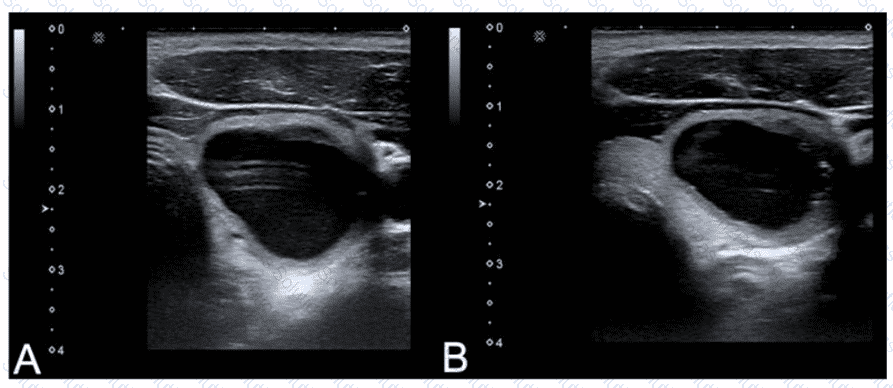

Which adjustment will reduce the artifact in the cystic lesion in image A resulting in image B?

A.

Turn off harmonics

B.

Increase dynamic range

C.

Turn on edge enhancement